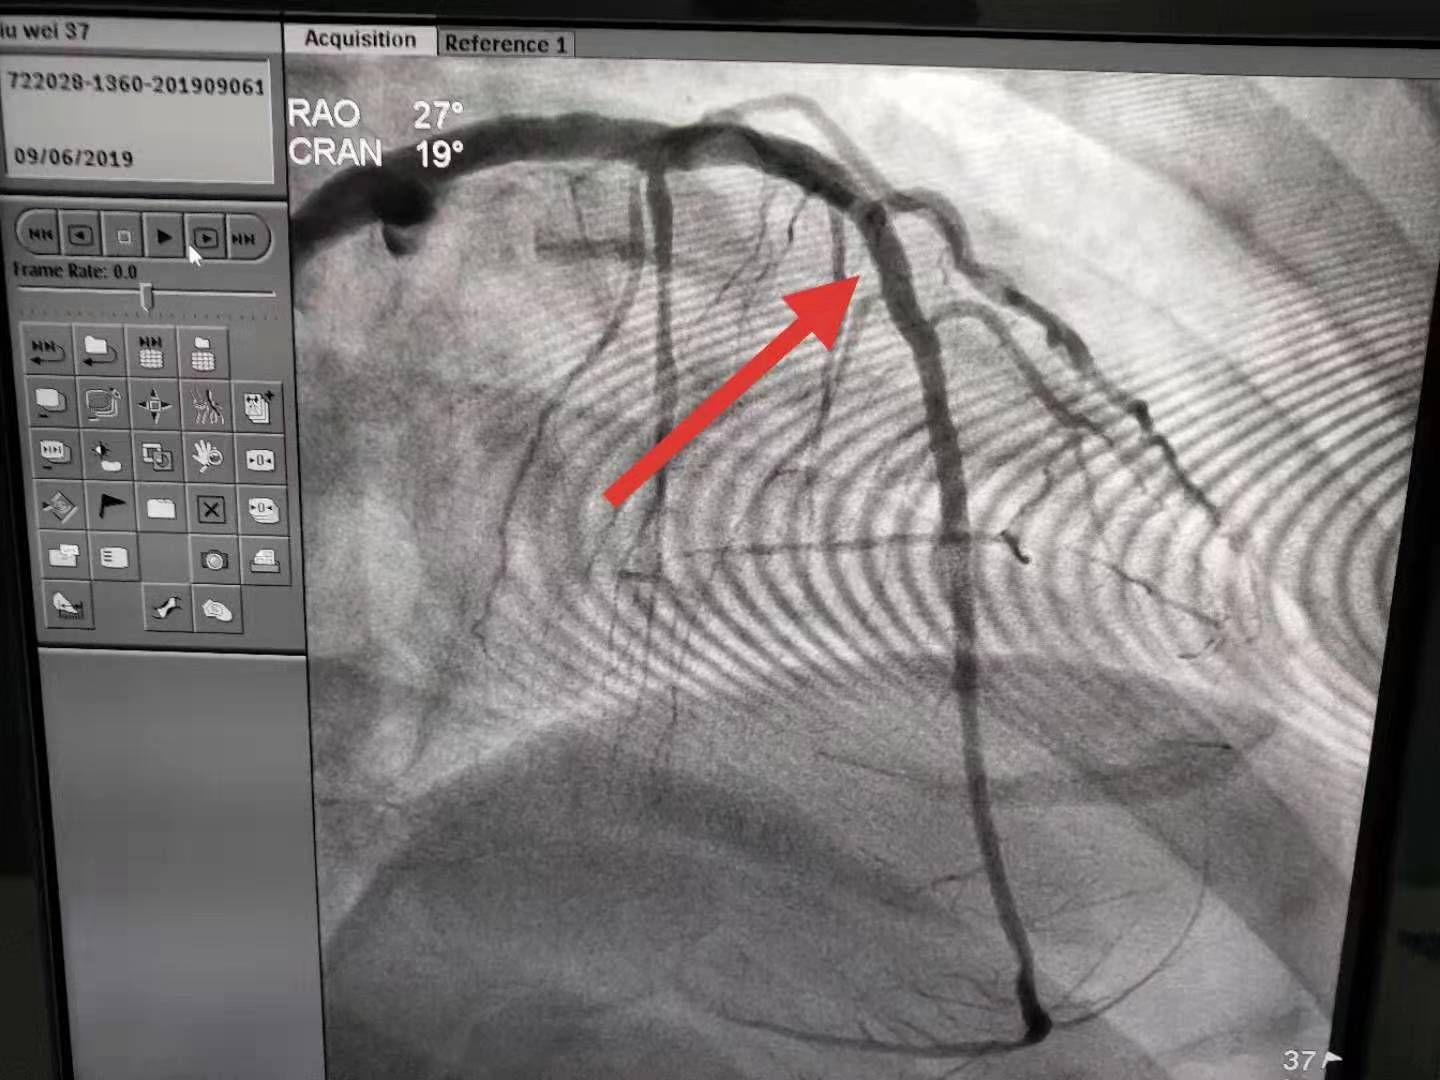

近日,一位患者突发心前区不适伴心慌,市人民医院急诊科医护人员迅速出诊,心电图提示急性下壁ST段抬高型心肌梗死,立即口服“心梗一包药”并监测生命体征,启动胸痛绿色通道,行急诊冠脉造影术,发现右冠状动脉闭塞,开通了梗死的靶血管,植入1枚支架,患者转危为安,术后恢复良好。

急性心肌梗死(AMI)是冠状动脉血流中断或减少,导致相应心肌细胞缺血坏死,是目前影响人类健康以及致死、致残的主要疾病之一。随着经济发展及生活方式改变,我国AMI的发生率持续增长。早期、快速地再灌注治疗是改善AMI患者预后的关键。而介入治疗因其微创、并发症少,血管开通率高等特点成为治疗急性心肌梗死的主要治疗手段。我院自开展急诊冠脉介入后不断优化流程,缩短患者血管开通时间,挽救濒死心肌,改善患者预后。